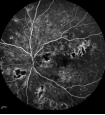

2.png

糖网的视网膜血管渗漏